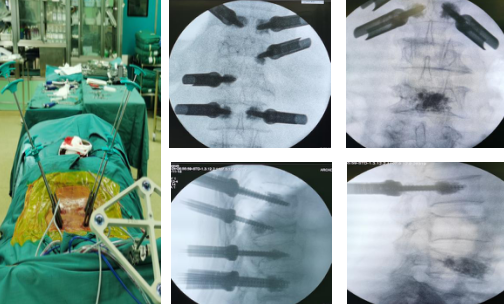

在天玑机器人的精确定位下,手术团队沿着套筒钻入导针,确认位置无误后,再沿导针拧入单平面骨水泥螺钉,注入骨水泥;待骨水泥凝固,上连接棒,撑开,实施减压手术;手术在骨科机器人的精准导航下,顺利完成,实现了手术的微创化、精准化、智能化。

定位,标记,扫描传送规划,钻入导针

拧入单平面骨水泥螺钉,注入骨水泥

“这台手术,如果采用传统手术方式,需要切开近20厘米的切口,有了‘天玑’机器人的辅助,只在患者腰椎两侧各切开几个1厘米左右的切口,利用天玑强大的光学追踪系统和灵活稳定的机械臂进行操作,精准度达到0.8毫米,手术用时也缩短了三分之一。”孟磊医生说,由于伤口小、出血量少,患者术后恢复时间也大大缩短。